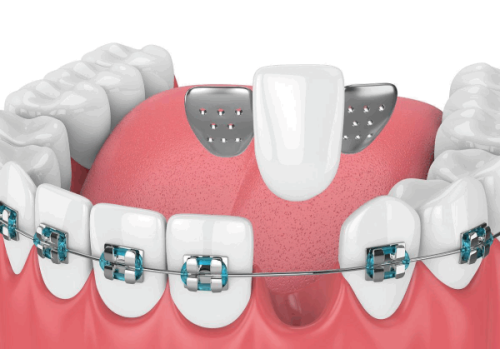

康斯坦丁医生深耕口腔种植及修复领域多年,技术扎实全面,拥有深厚的德国口腔诊疗技术背景,不仅是德国Ankylos种植系统培训师、德国SDS种植体研发医生团成员,还参与德国FORESTADENT非凡正畸专项技术研发。他耐心细致,擅长和患者沟通,能根据患者口腔情况制定个性化诊疗方案,具备处理各类复杂口腔种植病例的能力,还能将国际先进的种植技术与国内患者口腔实际情况相结合,优化诊疗方案,提升治疗效果与患者体验,多年来深受患者喜爱,行业认可度颇高。